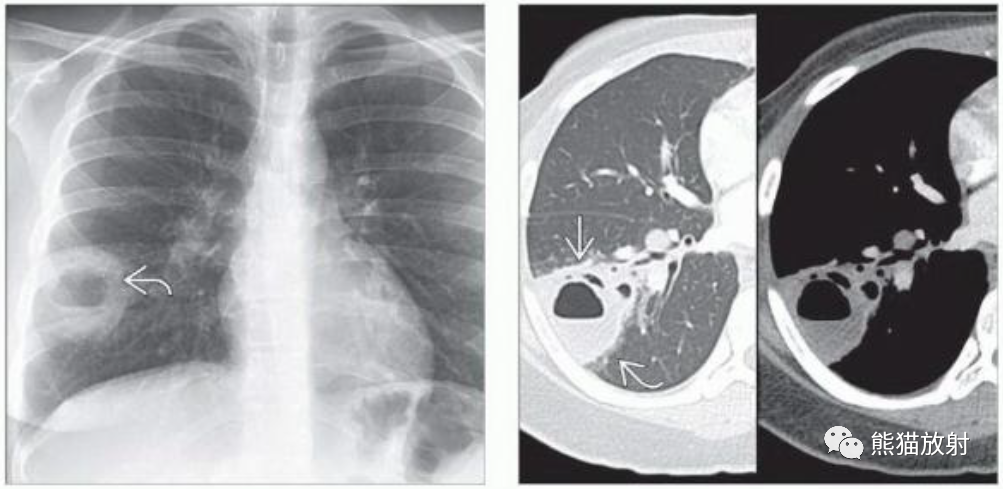

(左)免疫功能低下的肺隐球菌病患者,PA胸片显示右下肺野见一空洞性肿块,内见气液平面。

(右)同一患者,CECT肺窗和软组织窗图像显示右肺下叶空洞性肿块,内见气液平面,提示脓肿形成。邻近肺实质可见片状磨玻璃影(弯箭)。